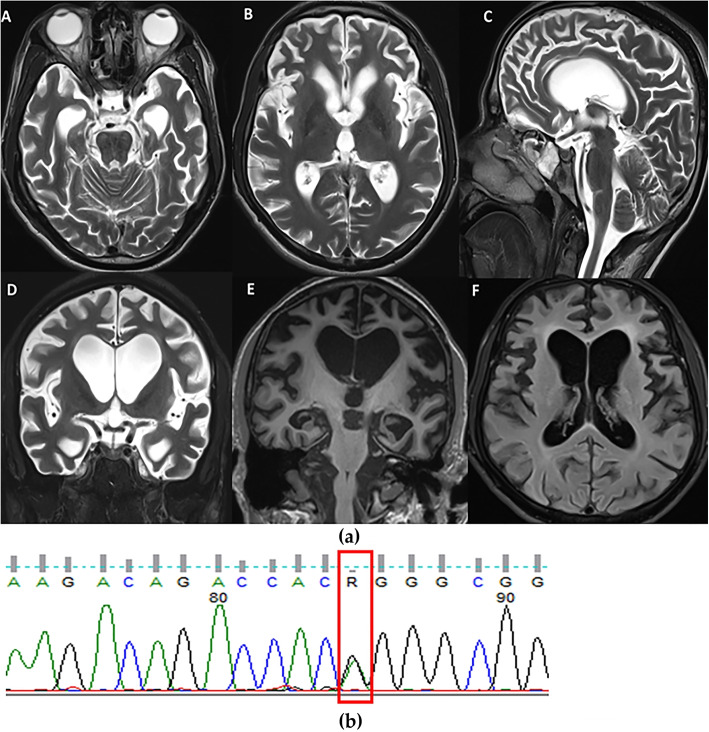

背景/目的:额颞叶痴呆(FTD)是早发性退行性痴呆的常见病因之一,是一种临床和病理异质性的神经退行性疾病。在全球范围内,微管相关蛋白Tau (MAPT)、前颗粒蛋白(GRN)和9号染色体开放阅读框72(C9orf72)是常见的FTD基因突变。然而,在印度还没有报道,到目前为止,只有一种前颗粒蛋白(PGRN)突变被报道。本研究旨在首次使用全外显子组测序(WES)描述来自印度额颞叶痴呆队列的7例FTD患者携带致病性MAPT突变的临床特征和放射学模式。方法:从南印度一所教学大学医院招募符合额颞叶痴呆标准的痴呆患者。所有患者均接受了详细的临床评估、神经影像学和全外显子组测序(WES)的遗传分析。结果:86例行WES的FTD患者中,7例有MAPT突变。值得注意的是,其中两个是新的变体。结论:在印度,WES首次报道了FTD的致病性MAPT,而且主要来自单一中心。确定致病的MAPT基因对于规划突变特异性临床试验和理解FTD遗传的伦理和文化差异非常重要。

Background/objectives: Frontotemporal Dementia (FTD) is one of the common causes of early-onset degenerative dementia and is a clinically and pathologically heterogeneous group of neurodegenerative disorders. Globally, Microtubule Associated Protein Tau (MAPT), progranulin (GRN), and Chromosome 9 open reading frame 72(C9orf72) are the common FTD genetic mutations. However, they have not been reported from India, and only one progranulin (PGRN) mutation has been reported so far. This study aims to describe the clinical features and radiological patterns of seven patients of FTD harbouring pathogenic MAPT mutations from an Indian cohort of Frontotemporal dementia, using whole-exome sequencing (WES) for the first time.

Methods: Subjects with dementia fulfilling the criteria for frontotemporal dementia were recruited from a teaching university hospital in South India. All of them underwent detailed clinical evaluation, neuroimaging, and genetic analysis by Whole Exome Sequencing (WES).

Results: Among 86 patients with FTD who underwent WES, seven had MAPT mutations. Notably, two are novel variants.